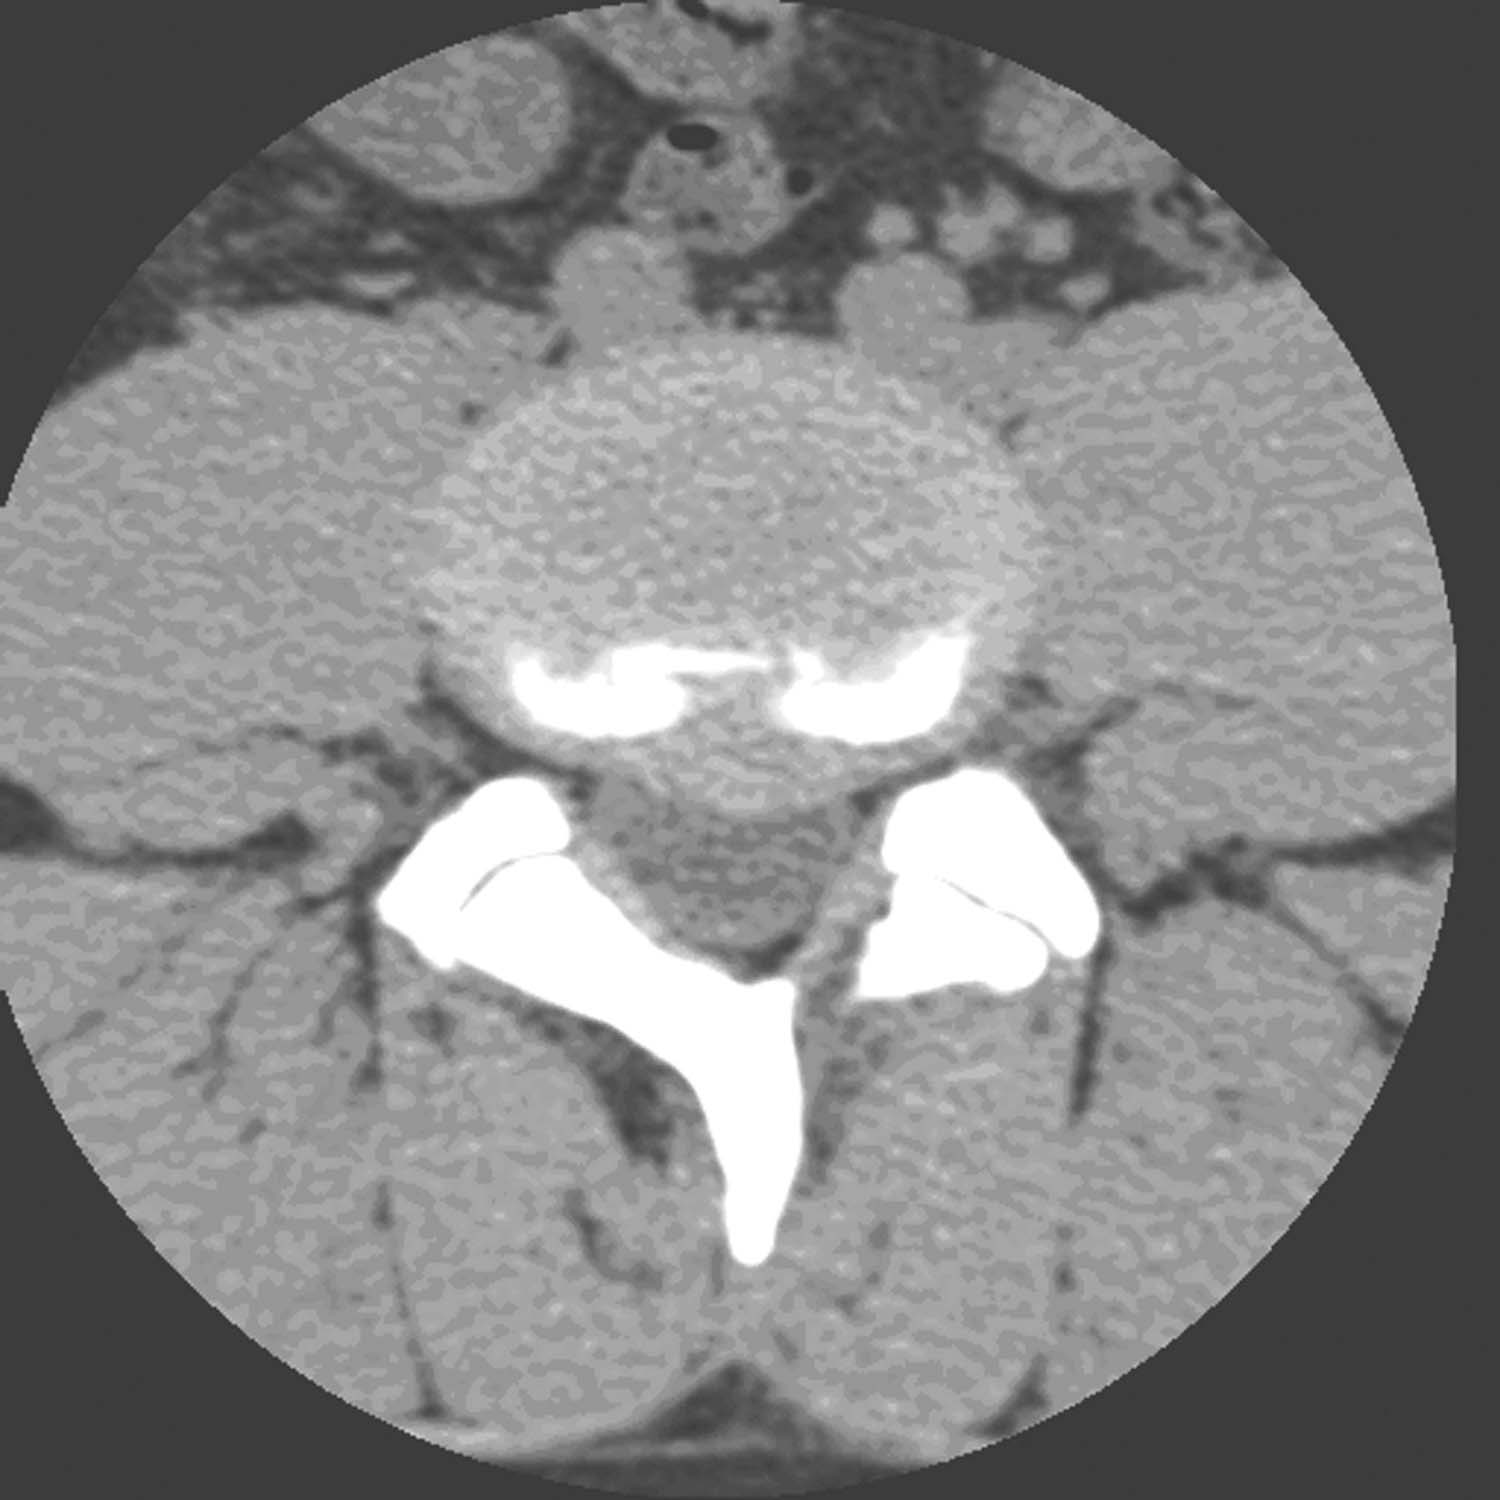

由于椎间盘退变,纤维环松弛,髓核组织脱水,使整个椎间盘失去弹性,椎间盘均匀向四周膨隆,超过椎体软骨板的边缘(图16-1-2)。此型纤维环无断裂,硬脊膜囊可有或无受压,患者可有或无神经根受压症状,但可出现腰痛。

图16-1-2 椎间盘膨出图示